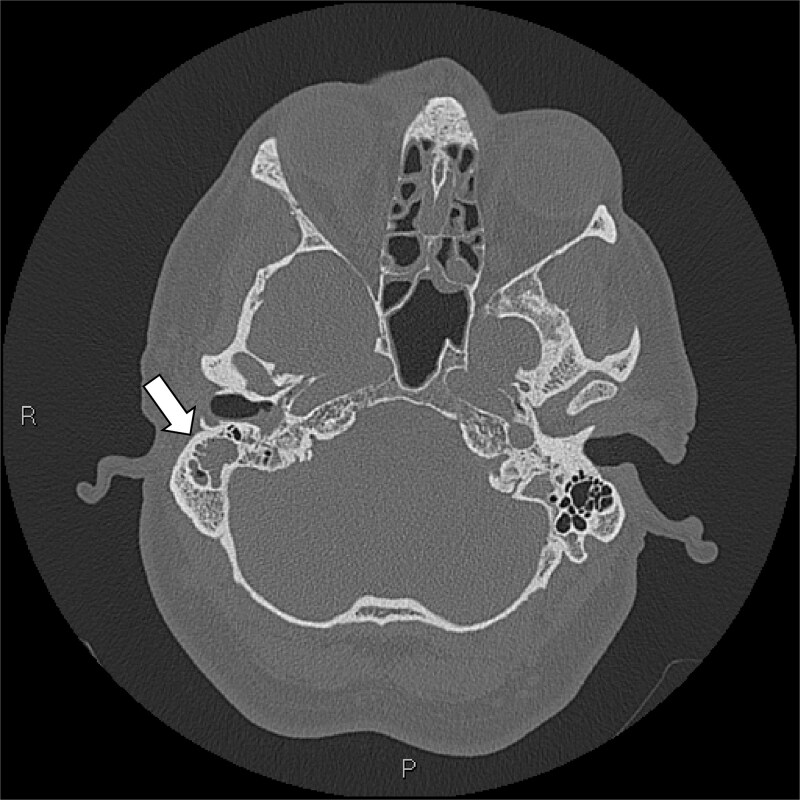

既往健康,免疫功能正常的中年男性,12小时右耳疼痛史,轻度流感样疾病后出院,到地区医院就诊。他的神经系统迅速恶化,瞳孔扩大,癫痫发作,需要插管。在紧急转至第四重症监护室后,多学科评估(耳鼻喉科和神经外科)、神经影像学和右耳鼓膜切开术证实耳瘤乳突炎合并脑静脉窦血栓形成。CT静脉造影显示广泛血栓形成,包括右乙状窦、横窦和上矢状窦。鼓膜切开术显示培养阴性血染脓。肺部微生物学结果对乙型流感和烟曲霉复合体呈阳性。尽管进行了最大限度的医疗治疗,患者还是出现了双侧静脉梗死、脑水肿和小脑扁桃体突出,并在48小时内进展为脑死亡。器官捐赠按照患者先前的意愿进行。即使在健康个体中,耳乳突炎也可引起快速、致命的颅内并发症,因此需要早期影像学检查、专家介入和警惕神经功能衰退。

A previously healthy, middle-aged immunocompetent man presented to a regional hospital with a 12-h history of right ear pain and discharge following a mild flu-like illness. He rapidly deteriorated neurologically, developing dilated pupils and seizures requiring intubation. Following urgent transfer to a quaternary ICU, multidisciplinary assessment (ENT and Neurosurgery), neuroimaging, and right ear myringotomy confirmed Otomastoiditis with catastrophic cerebral venous sinus thrombosis. CT venography demonstrated extensive thrombosis involving the right sigmoid, transverse, and superior sagittal sinuses. Myringotomy revealed culture-negative blood-stained pus. Pulmonary microbiology results were positive for Influenzae B and the Aspergillus fumigatus complex. Despite maximal medical management, the patient developed bilateral venous infarctions, cerebral edema, and cerebellar tonsillar herniation, progressing to brain death within 48 h. Organ donation proceeded in accordance with his prior wishes. Otomastoiditis can cause rapid, fatal intracranial complications even in healthy individuals, highlighting the need for early imaging, specialist input, and vigilance for neurological decline.